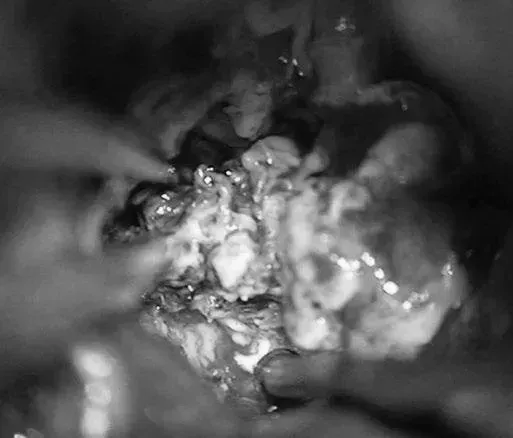

▼移除AVM